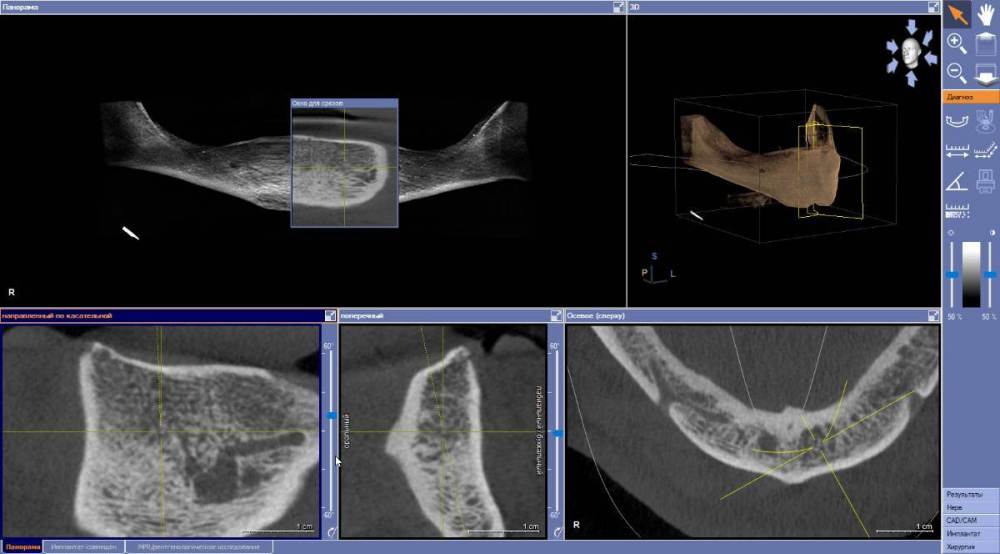

Estes Опубликовано 6 апреля, 2022 Автор Поделиться Опубликовано 6 апреля, 2022 Здравствуйте. Вот подошел ко мне пациент с полной адентией на в/ч и н/ч. На в/ч ПСП держится нормально, на н/ч - не носит. Подскажите - установка 4х имплантов 44-42-32-34 и дальнейшее протезирование например съемным на балке тут показано? Есть ли необходимость сравнять гребень во фронтальном отделе? Соотношение челюстей в целом таково, что места весьма прилично для съемника на балке. Еще подскажите, какие осложнения могут в принципе быть при установке импланта в резцовую ветвь - у пациента что-то они выражены? И вот что за трещинки в теле челюсти язычно - на фото стрелками показал ? 2022-04-06_08-22-32.mp4 Ссылка на комментарий

Irouil Опубликовано 6 апреля, 2022 Поделиться Опубликовано 6 апреля, 2022 Трещинки - мелкие сосуды Осложнения обычные - кровотечения в процессе операции, болевой синдром в случае развития неврита - после Ссылка на комментарий